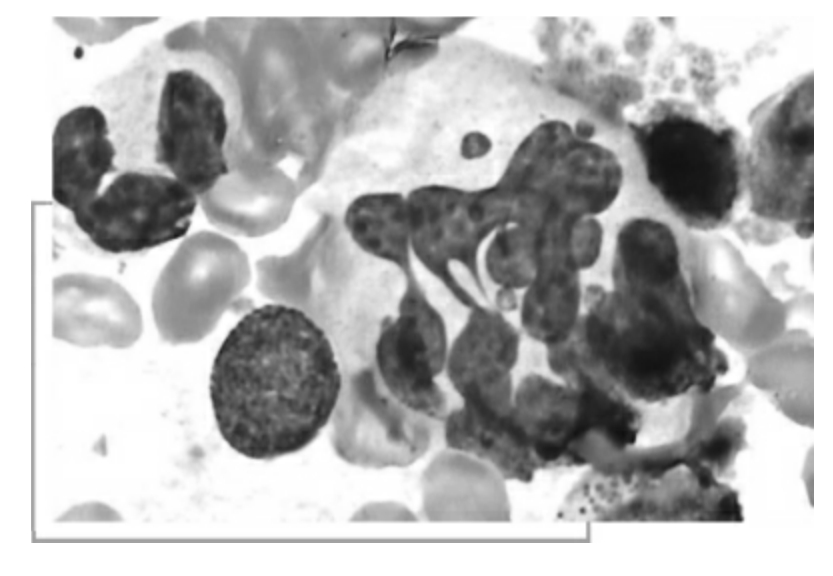

人体内专职吞噬细胞分为2类:①小吞噬细胞,主要是中性粒细胞,还有嗜酸性粒细胞;②大吞噬细胞即单核吞噬细胞系统,包括末梢血液中的单核细胞和淋巴结、脾、肝、肺以及浆膜腔内的巨噬细胞、神经系统内的小胶质细胞等。

中性粒细胞